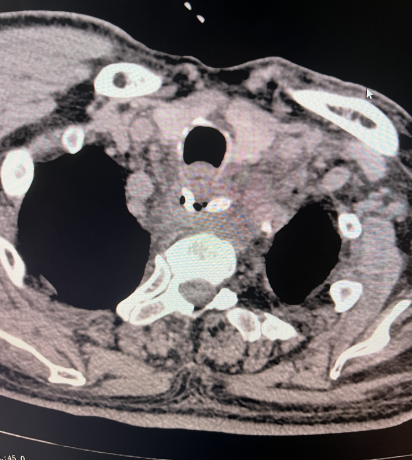

第一例患者,女性,5岁,吞入硬币

2、CT检查能够直接显示异物的形态、大小、位置以及与周围组织的关系,如与大血管等重要结构之间的相对位置。方法是通常采用静脉注射碘造影剂后立即行CT扫描,有时需分次摄片以观察不同时间点的影像变化。特点:CT检查具有较高的分辨率和准确性,能够检测出较小的异物和潜在的并发症,如食管穿孔、周围脓肿或炎症等。